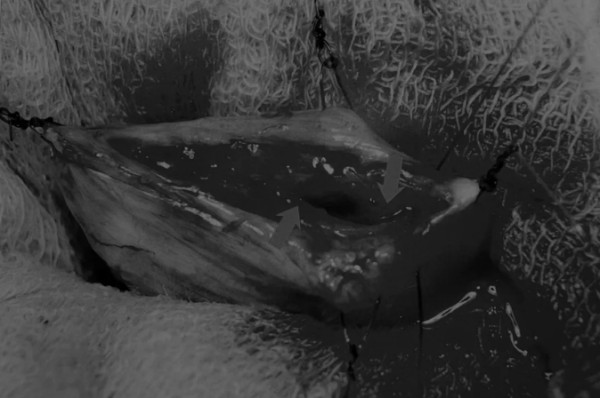

在中线开腹手术后,确定膀胱,将其取出并隔离(图1)。为了使膀胱持续暴露,可在膀胱中线两侧各放置一根固定缝线(图2)。

图2 在手术过程中,还需要另外两根固定缝线来保持膀胱切开术的膀胱边缘处于暴露状态